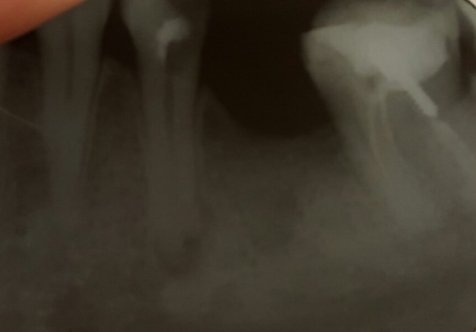

У меня воспалилась нижняя десна, и надулась шишка между языком и десной. После семидневного лечения антибиотиками шишка уменьшилась, но при пальпации десна болит. Сегодня после рентгена врач вынес вердикт об удалении седьмого и восьмого зубов из-за наличия гнойных мешков на корнях. Но болит у меня десна не под этими зубами, а под тем местом, где раньше у меня был шестой зуб. И боль при прощупывании возникает и глубоко под языком. Правда восьмой зуб во время еды болит.

Если под седьмым и восьмым зубами в надкостнице или, правильнее сказать, на верхушках имеется киста (гной), то, естественно, эти зубы подлежат удалению и являются причиной беспокойства. Также воспалительный процесс может распространяться по надкостнице. Обратитесь к альтернативному мнению хирурга и, если диагноз подтвердится, то следуйте рекомендациям.